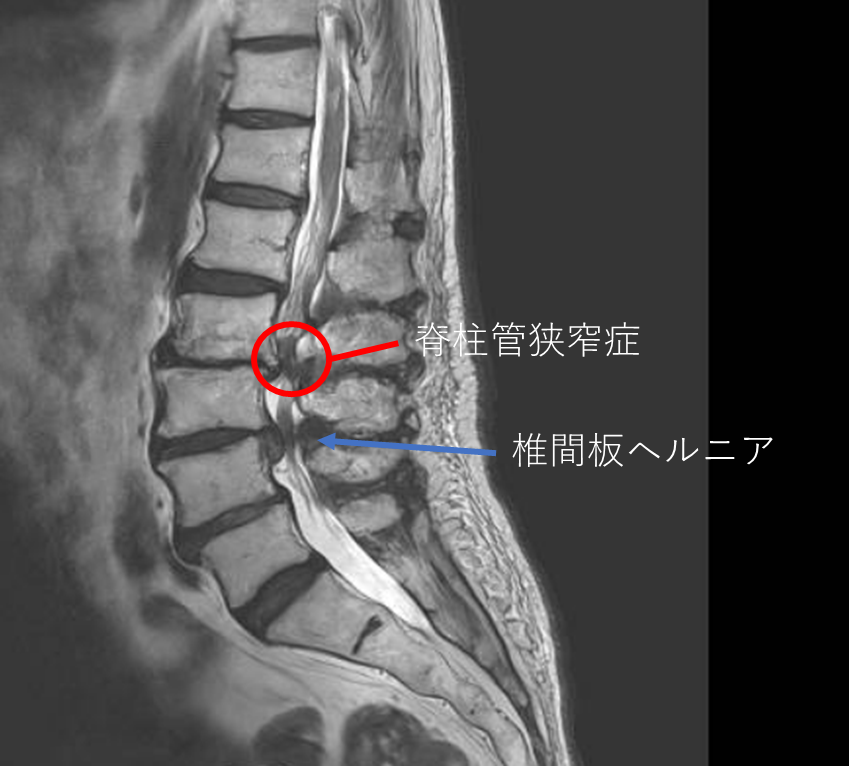

画像及び所見について

- L1/2,2/3,3/4,4/5,5/s-椎間板変性

- L3/4-椎間板ヘルニア

- L3/4-脊柱管狭窄症

以上の事が画像上認められます。

・L3/4-椎間板ヘルニアを認め、症状を鑑みると主症状の原因の可能性が高い